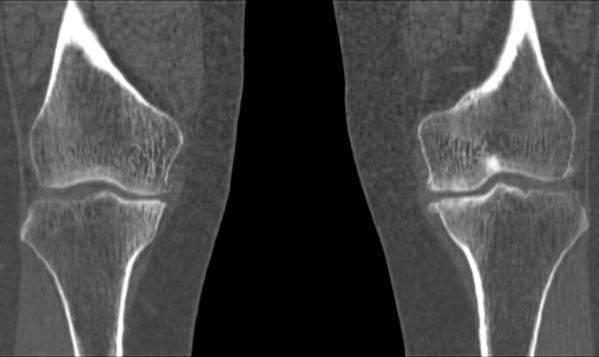

Медицинские снимки: рентген коленного сустава при остеопорозе